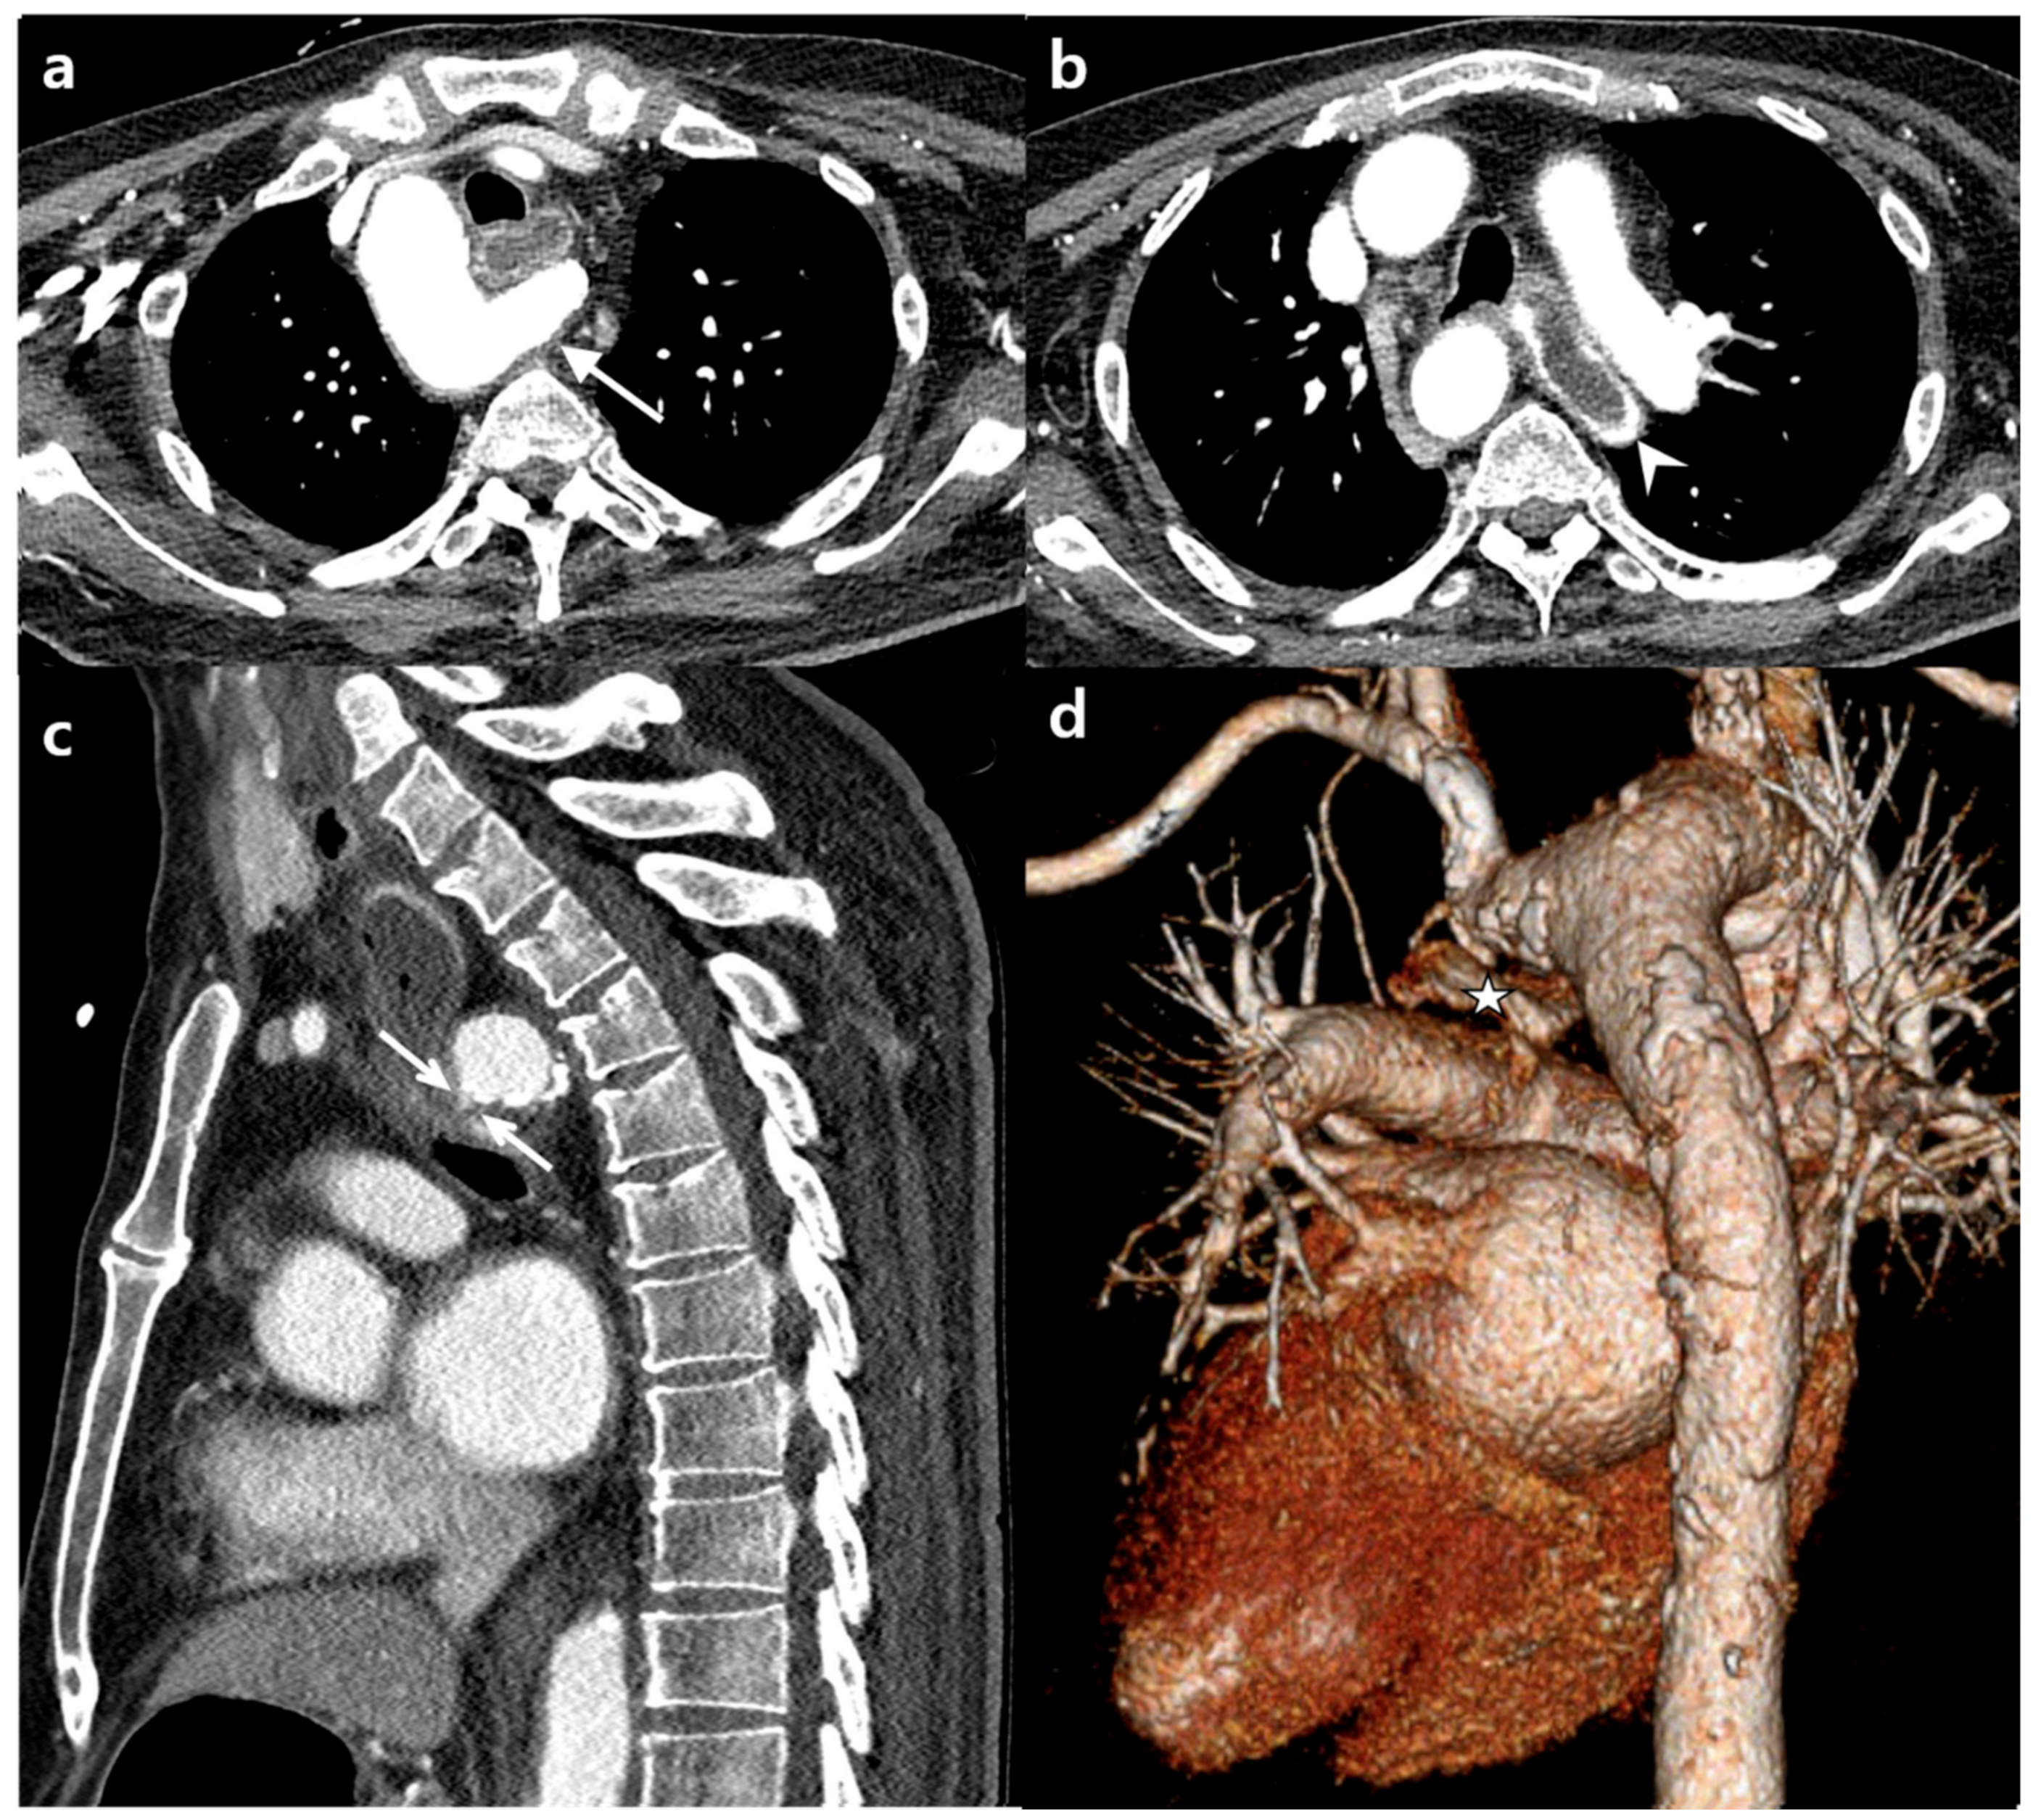

2. Case Report